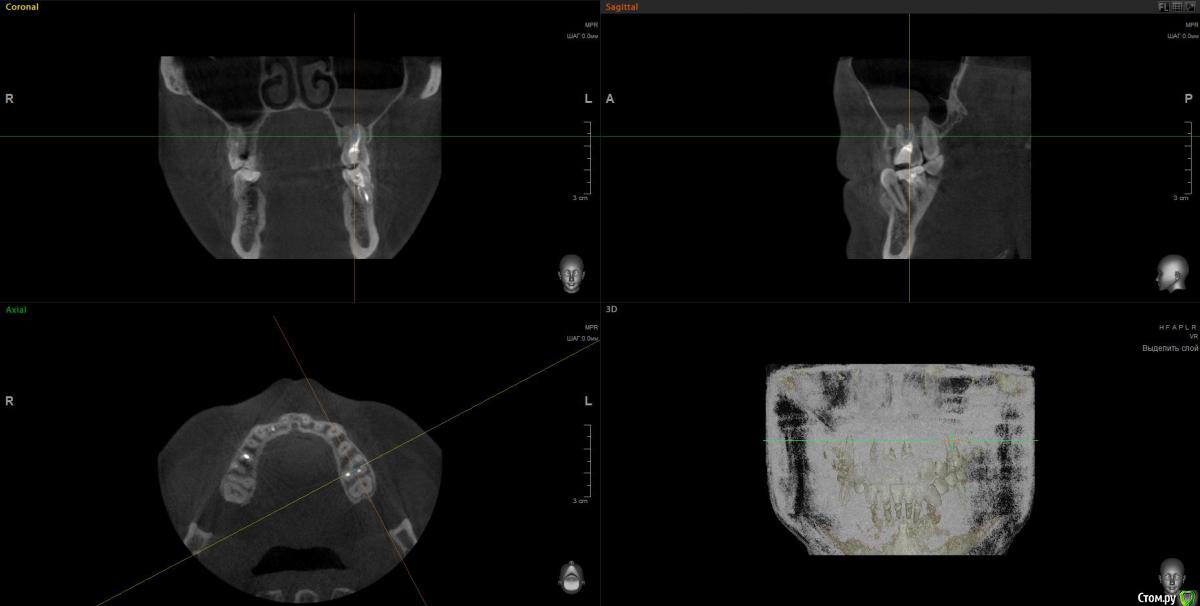

Гарриевич Опубликовано 12 декабря, 2016 Поделиться Опубликовано 12 декабря, 2016 Начните с лечения 6 зуба, так как по Кт он является возможной причиной процесса Ссылка на комментарий

wladdX Опубликовано 13 декабря, 2016 Поделиться Опубликовано 13 декабря, 2016 Несколько скриншотов. Ссылка на комментарий

red_butler Опубликовано 13 декабря, 2016 Поделиться Опубликовано 13 декабря, 2016 Лор назначает консервативное лечение с целью снятия обострения, лечите зуб и диспансерно наблюдаетесь. 1 Ссылка на комментарий